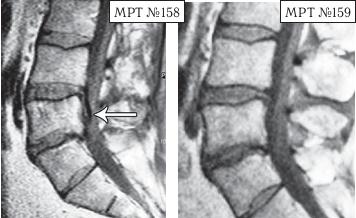

МРТ № 3

На МРТ № 3 — поясничный отдел позвоночника. (На данном «контрольном» снимке наблюдаются остаточные явления дегенеративно-дистрофического процесса в сегменте LV-SI после устранения методом вертеброревитологии секвестрированной грыжи межпозвонкового диска.)

В поясничном отделе форма позвоночного канала, создаваемая телом и дужками позвонка, вариабельна, но чаще она пятиугольная. В норме позвоночный канал в пояснично-крестцовом отделе сужен в переднезаднем диаметре на уровне LIII и LIV позвонков. Его диаметр каудально увеличивается, и поперечное сечение канала приобретает форму, близкую к треугольной, на уровне LV-SI. У женщин канал имеет тенденцию к расширению в нижней части крестцовой области. Сагиттальный диаметр значительно уменьшается от LI к LIII почти неизменен от LIII к LIV и увеличивается от LIV к LV. В норме переднезадний диаметр позвоночного канала в среднем равен 21 мм (15–25 мм).

Существует простая и удобная формула определения ширины позвоночного канала:

нормальный сагиттальный размер не менее 15 мм;

11–15 мм — относительный стеноз;

менее 10 мм — абсолютный стеноз. Уменьшение этого соотношения свидетельствует о сужении канала.

Высота поясничных межпозвонковых дисков 8–12 мм, нарастает от LI до LIV-LV, обычно уменьшается на уровне LV-SI